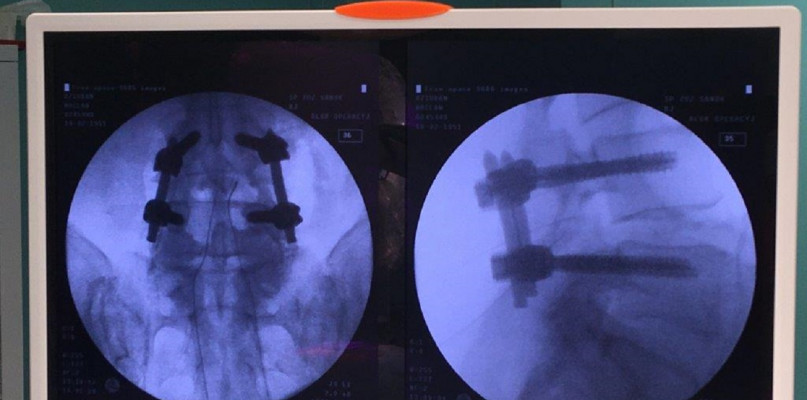

Dnia 10.01.2020 w Szpitalu w Sanoku neurochirurdzy Robert Konior i Marcin Czternastek wykonali zabieg operacyjny u pacjenta ze stenozą kanału kręgowego w odcinku lędźwiowym techniką minimalnie inwazyjną. Lekarze w pierwszej kolejności mikrochirurgicznie odbarczyli struktury nerwowe kanału kręgowego, a następnie dokonali przezskórnej stabilizacji kręgosłupa nowoczesnymi tytanowymi implantami. Operacja przebiegła bez powikłań a pacjent czwartego dnia opuścił szpital będąc samodzielny. Powyższa technika umożliwia uruchamianie pacjenta już następnego dnia po operacji i szybki powrót do sprawności ( dwukrotnie szybszy niż w przypadku technik klasycznych).